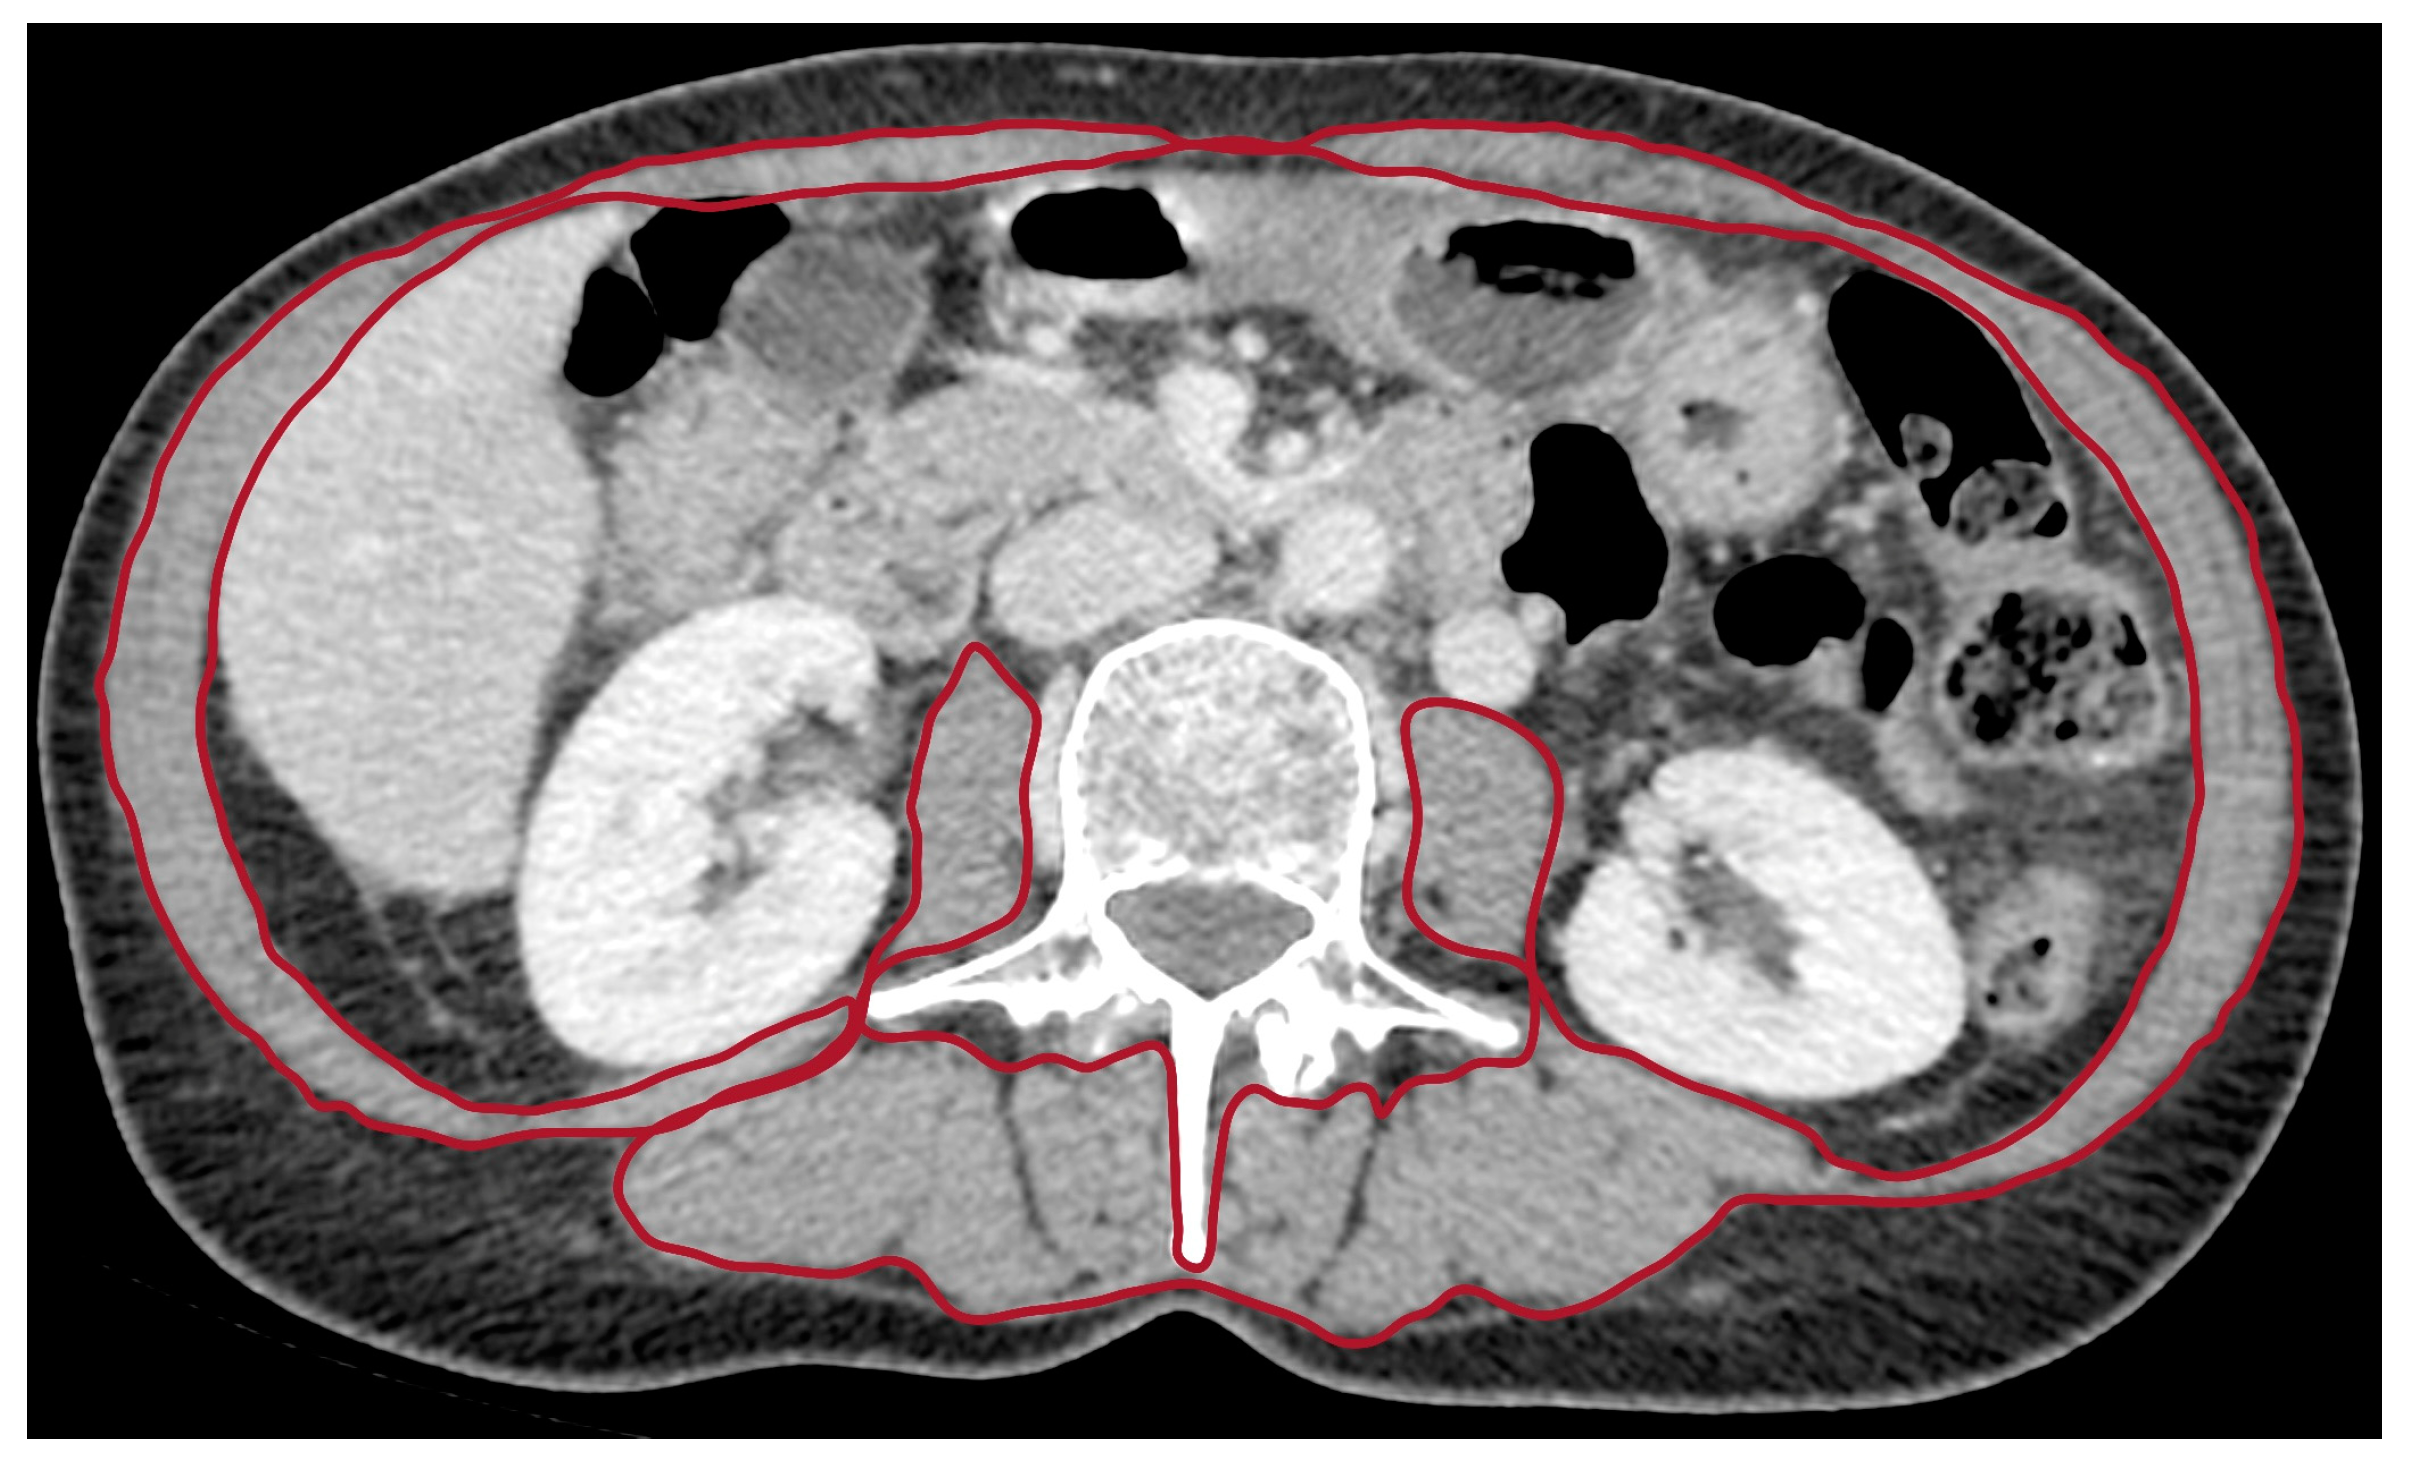

2.4. Anthropometric Measurement

2.5. Image Analysis